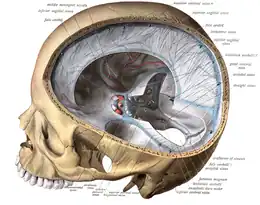

Venous drainage

The venous drainage of the cerebrum can be separated into two subdivisions: superficial and deep.

- The superficial system

The superficial system is composed of dural venous sinuses, sinuses (channels) within the dura mater. The dural sinuses are therefore located on the surface of the cerebrum. The most prominent of these sinuses is the superior sagittal sinus which is located in the sagittal plane under the midline of the cerebral vault, posteriorly and inferiorly to the confluence of sinuses, where the superficial drainage joins with the sinus that primarily drains the deep venous system. From here, two transverse sinuses bifurcate and travel laterally and inferiorly in an S-shaped curve that forms the sigmoid sinuses which go on to form the two jugular veins. In the neck, the jugular veins parallel the upward course of the carotid arteries and drain blood into the superior vena cava. The veins puncture the relevant dural sinus, piercing the arachnoid and dura mater as bridging veins that drain their contents into the sinus.[5]

- The deep venous system

The deep venous system is primarily composed of traditional veins inside the deep structures of the brain, which join behind the midbrain to form the great cerebral vein (vein of Galen). This vein merges with the inferior sagittal sinus to form the straight sinus which then joins the superficial venous system mentioned above at the confluence of sinuses.